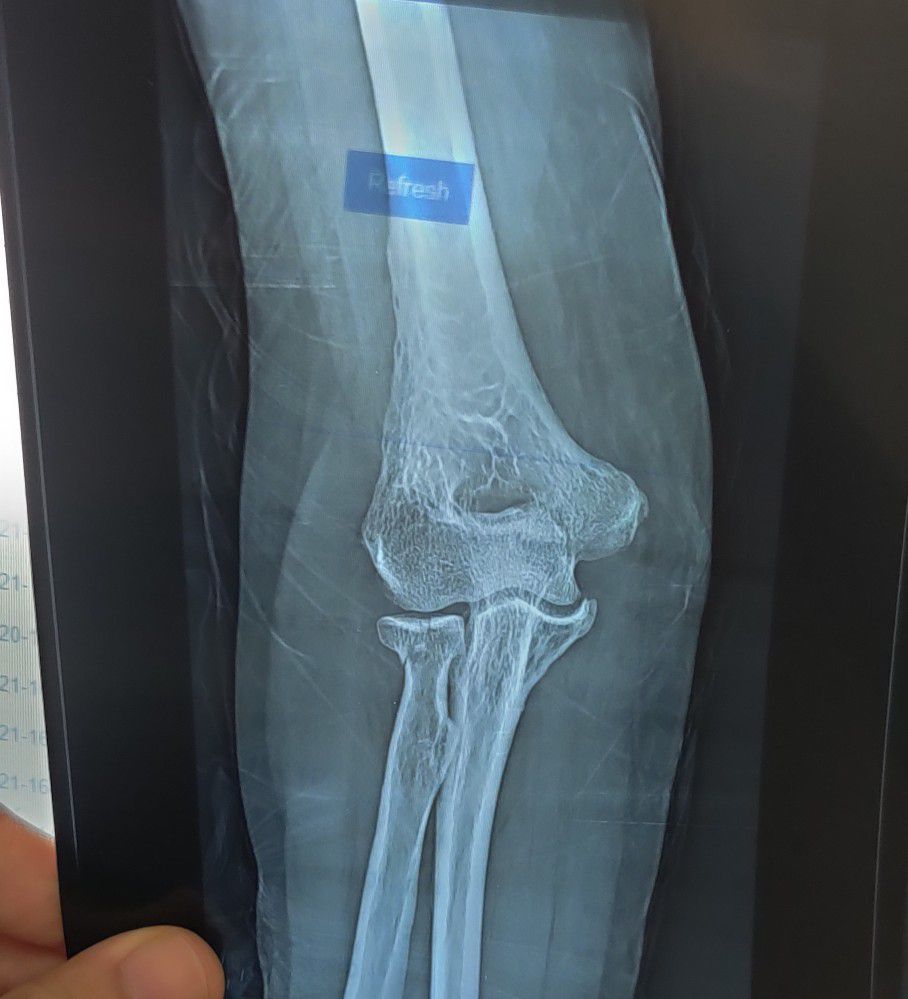

Radius Head Fracture

Fracture

Ortho

Radius